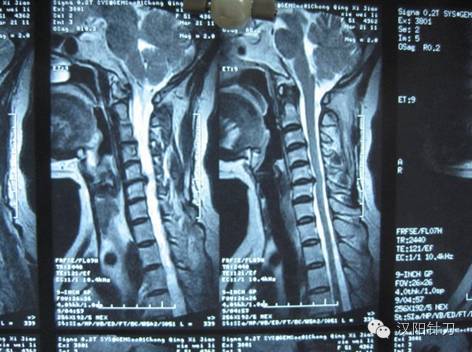

目前治疗颈椎病的方法众多,但疗效均不甚理想。临床实践证明,针刀治疗颈椎病在众多非手术疗法中近期疗效显著、远期疗效理想,应作为颈椎病首选治疗方法。

如何运用针刀精准治疗颈椎病?成为许多针刀医生的追求!